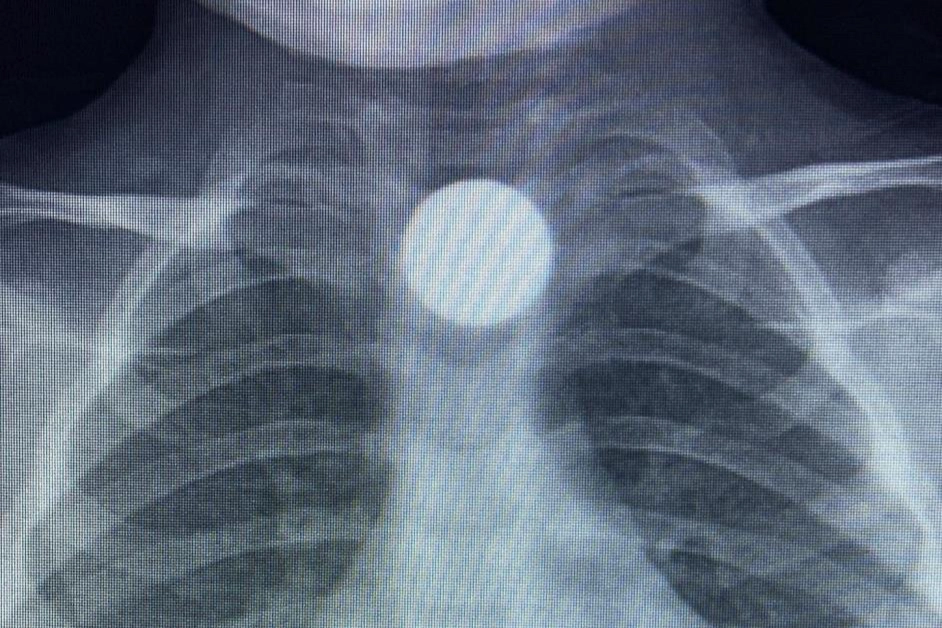

Olay, İnegöl'ün kırsal Yeniceköy Mahallesi'ndeki bir evde meydana geldi. 3 yaşındaki Bilal K., evde yerde bulduğu 50 kuruş madeni parayı ağzına atıp yuttu. Olayı fark eden ailesi tarafından çocuk özel araçla İnegöl Devlet Hastanesi'ne kaldırıldı. Yapılan tetkiklerde yemek borusunda takılı kalan madeni para görüldü. Çocuk ilk tedavinin ardından ambulansla Bursa Yüksek İhtisas Eğitim Ve Araştırma Hastanesi'ne sevk edildi.